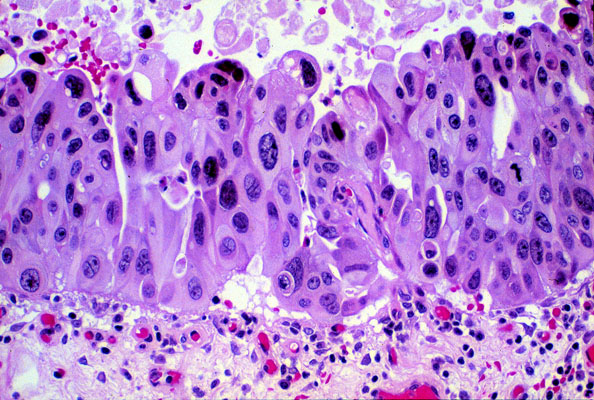

Carcinoma in situ, histology

The normal transitional epithelium has been replaced by thickened epithelium composed of cells that have hyperchromic nuclei and vary in size and shape. The nuclei show no polarization. These flat carcinoma-in-situ lesions are prone to endophytic growth and invasion of the bladder wall.